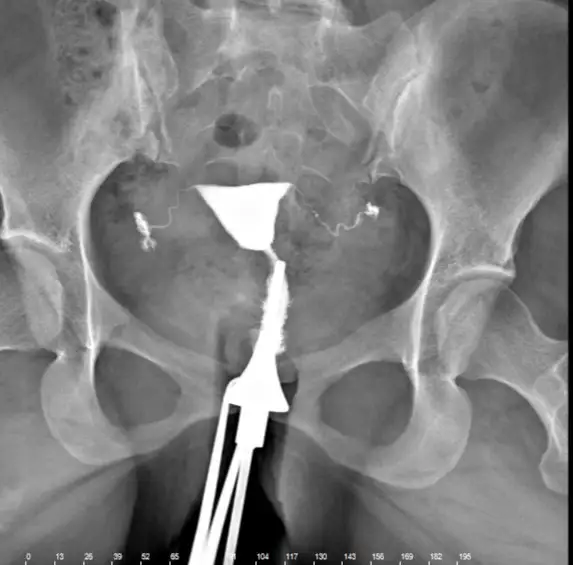

Arkadaşlar ben dört ay önce rahim filmi çektirdim ama doktor herşey normal dedi yolladı hızlıca güvenemedim anlayan var mı bir sıkıntı gören var mı?

Hayır canım Bi kağıt vermediler buna bakarak doktor herşey yolunda dedi ama hızlıca dedi çıktım arka arkaya hasta alıyordu hani bakınca perde var mı rahim kalp şeklinde mi y şeklinde mi gibi riskli şeyleri var mı anlayan var mı?

Canım tam emin değilim bilen varsa yazar ama gördüğüm kadarıyla normal görünüyor tüpler falan